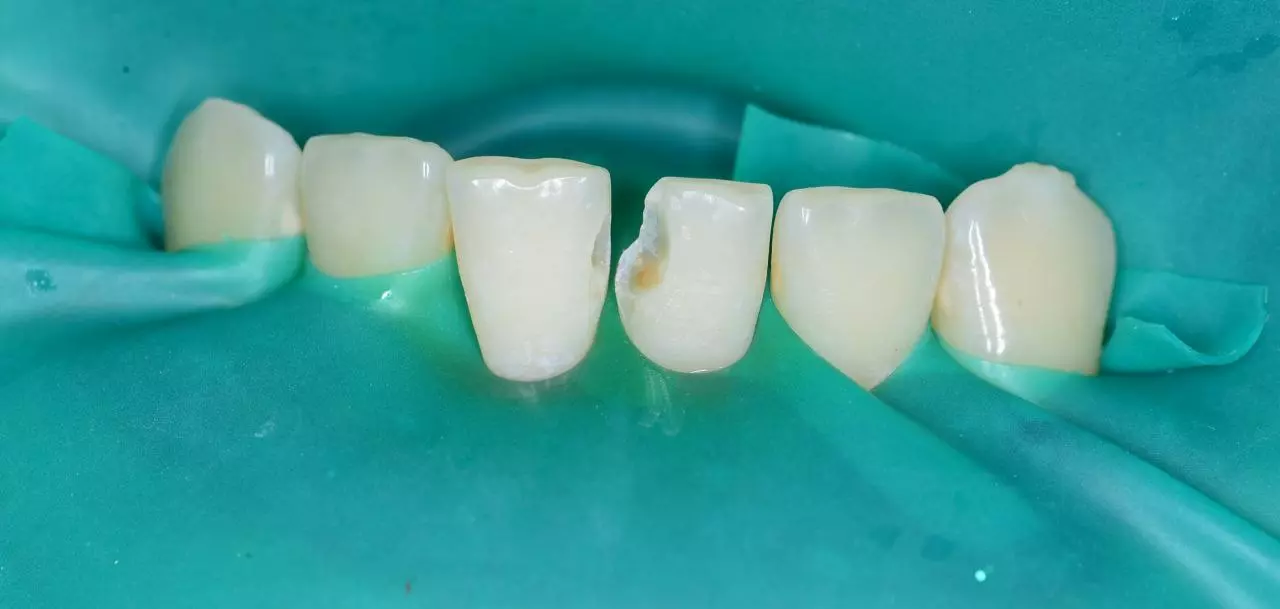

Лікування карієсу 41, вторинного карієсу 31.